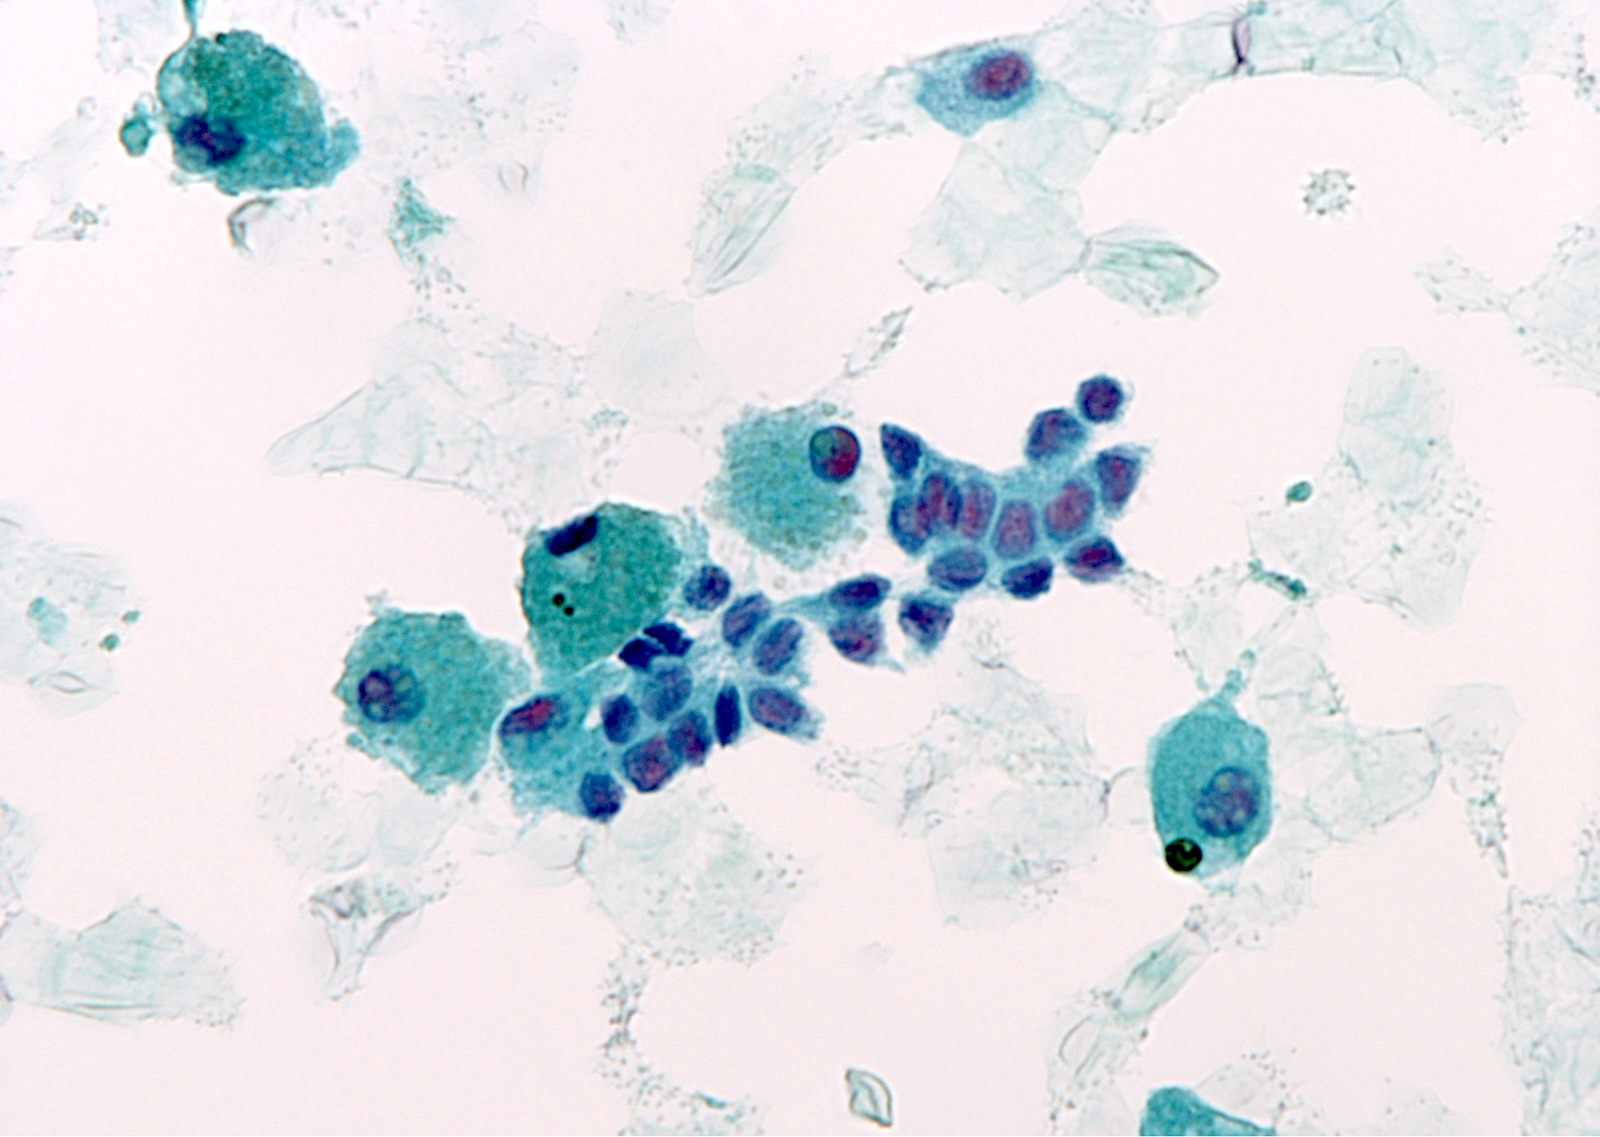

Cytology images

Contributed by Ayana Suzuki, Ph.D.

Explanatory notes

- AUS with nuclear atypia is associated with papillary thyroid carcinoma (28 - 56%) (Am J Clin Pathol 2011;136:572, Diagn Cytopathol 2012;40:410)

- Rare cells (< 20 cells) with enlarged, often overlapping nuclei, pale chromatin, irregular nuclear outlines and nuclear grooves

- Well defined, intranuclear pseudoinclusions or psammomatous calcifications (more suspicious) (Acta Cytol 2008;52:320)